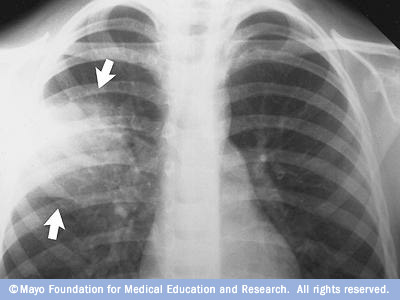

- Chest X-ray. This helps your doctor diagnose pneumonia and determine the extent and location of the infection. However, it can't tell your doctor what kind of germ is causing the pneumonia.